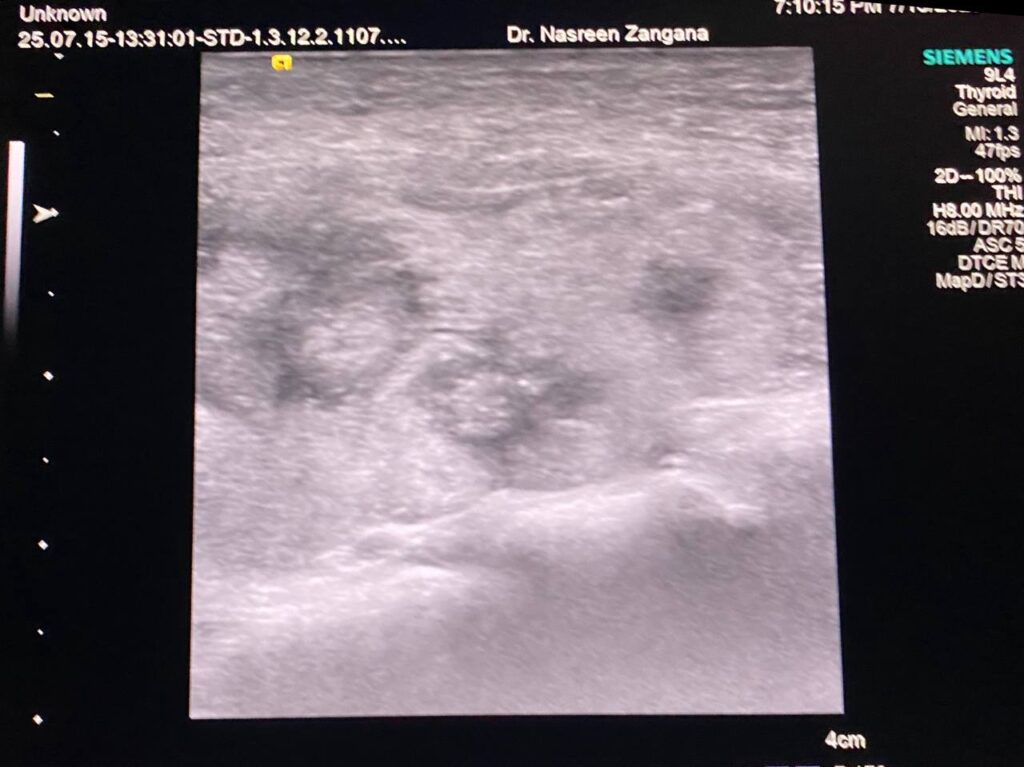

Thyroid U\S

The gland diffusely has lobulated outline, geographic heterogenous multiple hypo-echoic areas, ill-defined nodules < 3mm in sizes, with inter-digitating fibrosis, interrupted capsule, Picture of Hashimoto’s thyroiditis , left lobe contain ill distinct margin mass , its size 18.5×15.5mm, bulging the capsule , with irregular lateral margin , vascular on color Doppler , contain microcalcification , other two adjacent hypoechoic irregular masses are seen 11.8×7.8mm (also contain microcalcifications) & 4.7×3.8mm , all are mostly suspicious TIRADS 4 , please for further study